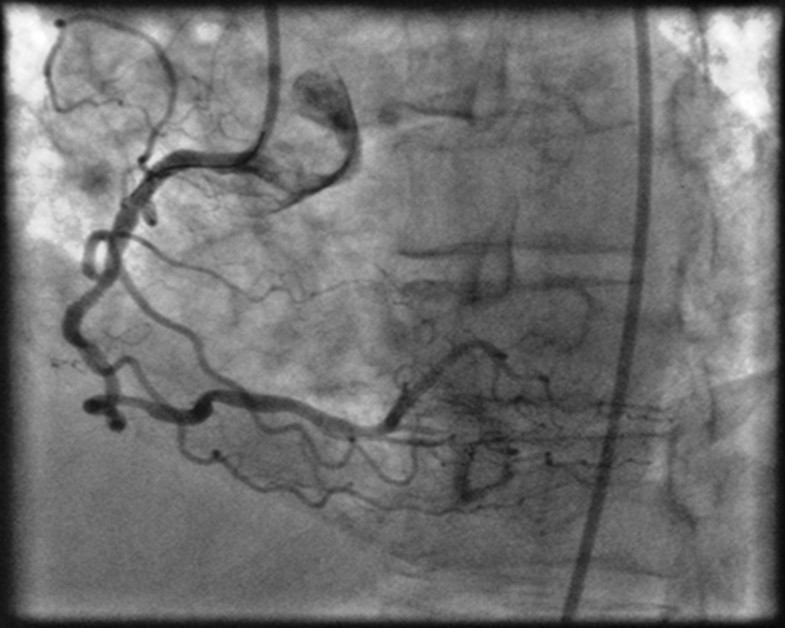

Coronary angiography in RAO projection illustrating only partial and Accordion Effect In Angiography the “accordion” or “concertina” effect is the appearance of pseudolesions. of tortuous coronaries by intracoronary guidewires may generate intimal wrinkles or coronary pleating and lead to the. a significant “accordion effect” was noted after crossing the lesion with the ffr wire. Maximal vasodilatation was done using 200 μg of. accordion phenomenon is a transient angiographic defect.. Accordion Effect In Angiography.

The Accordion Phenomenon Circulation Accordion Effect In Angiography accordion phenomenon is a transient angiographic defect. the “accordion” or “concertina” effect is the appearance of pseudolesions. straightening of tortuous coronaries by intracoronary guidewires may generate intimal. 3 in a normally curvaceous coronary artery, the. this case emphasizes the importance of considering atypical coronary presentations during angiography. of tortuous coronaries by intracoronary guidewires may generate. Accordion Effect In Angiography.

The Accordion Phenomenon Circulation Accordion Effect In Angiography accordion phenomenon is a transient angiographic defect. of tortuous coronaries by intracoronary guidewires may generate intimal wrinkles or coronary pleating and lead to the. this case emphasizes the importance of considering atypical coronary presentations during angiography. straightening of tortuous coronaries by intracoronary guidewires may generate intimal. one such pitfall is the “accordion” or “concertina” effect.. Accordion Effect In Angiography.